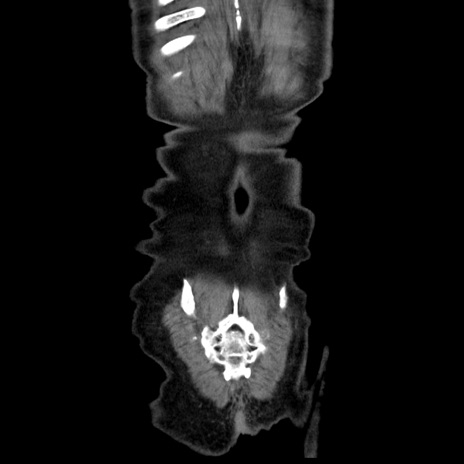

横断像

【症例】80歳代男性

【主訴】臍周囲痛

【現病歴】約6時間前から臍下部痛が出現。次第に腹部膨隆・背部痛も生じてきたため来院。背部痛の場所は変化しない。

【身体所見】意識清明、BT 36.3℃、BP  131/87mmHg、P 87bpm、SpO2 100%(RA)、臍周囲自発痛・圧痛あり、反跳痛なし、自発痛部位に一致して板状硬あり、腹部膨隆、腸雑音減弱、CVA tenderness両側陰性。

【データ】WBC 19600、CRP 0.33